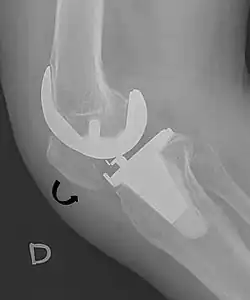

For recurrent patellar dislocations or cases with chronic instability, surgical intervention may be necessary. Patella stabilization surgery aims to restore proper kneecap tracking and reduce the risk of future dislocations.[4] Surgical options include reconstruction of the medial patellofemoral ligament (MPFL), realignment procedures such as osteotomy, and soft tissue adjustments around the patella.[4] MPFL reconstruction typically involves harvesting a hamstring tendon, commonly the gracilis, to create a new ligament that is positioned anatomically and secured with suture anchors.[4]

Recovery from patella stabilization surgery typically requires six to eight weeks, during which patients may need to use crutches initially and follow a structured physical therapy program to regain range of motion and strengthen the surrounding musculature.[4]